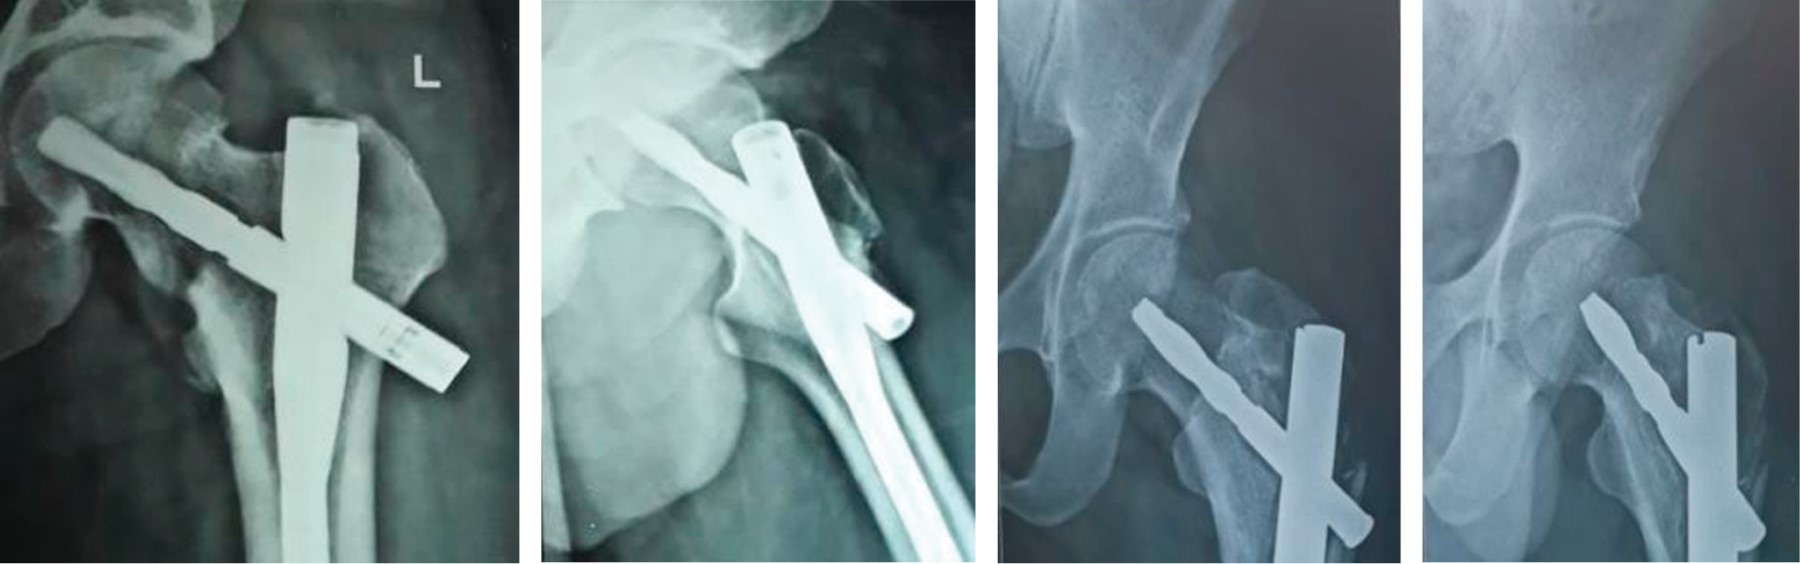

Implant related complications like screw back out (Figure 1), guide wire breakage (Figures 2 and 3), Z effect (Figure 4), TAD outliers (Figure 5) were more in PFN group whereas lateral screw protrusion, locking mechanism failure and barrel disengagement was more in PFNA2 group as shown in Figures 6, 7, 8 and 9. Neck shaft valgus outliers are more common in PFN group (Figure 10).

Implant-related complications, such as screw back-out, guidewire breakage, and proximal protrusion, were more pronounced in the PFN group, whereas lateral screw protrusion and medial migration were notable in the PFNA2 group.24 Lateral screw protrusion was observed in four patients in the PFNA2 group and one patient in the PFN group at the final follow-up in our study. Hu et al suggested a morphological mismatch in the Asian population between the proximal fragment of PFNA2 and the greater trochanter, leading to post-operative lateral trochanter pain.24

Maintaining the neck-shaft angle difference between the operated and normal side to less than 5° is necessary for better outcomes.29 In our study, varus malalignment and Limb Length Discrepancy (LLD) were associated with a neck shaft angle difference of 10° and 5° in the PFNA and PFN groups, respectively. Neck shaft angle outliers were more common in the PFN group (Figure 10), likely to achieve better proximal screw purchase and to avoid postoperative varus collapse, whereas outliers in TAD were more common in the PFNA group, possibly due to difficulty in differentiating between the screwdriver tip and screw head while engaged.